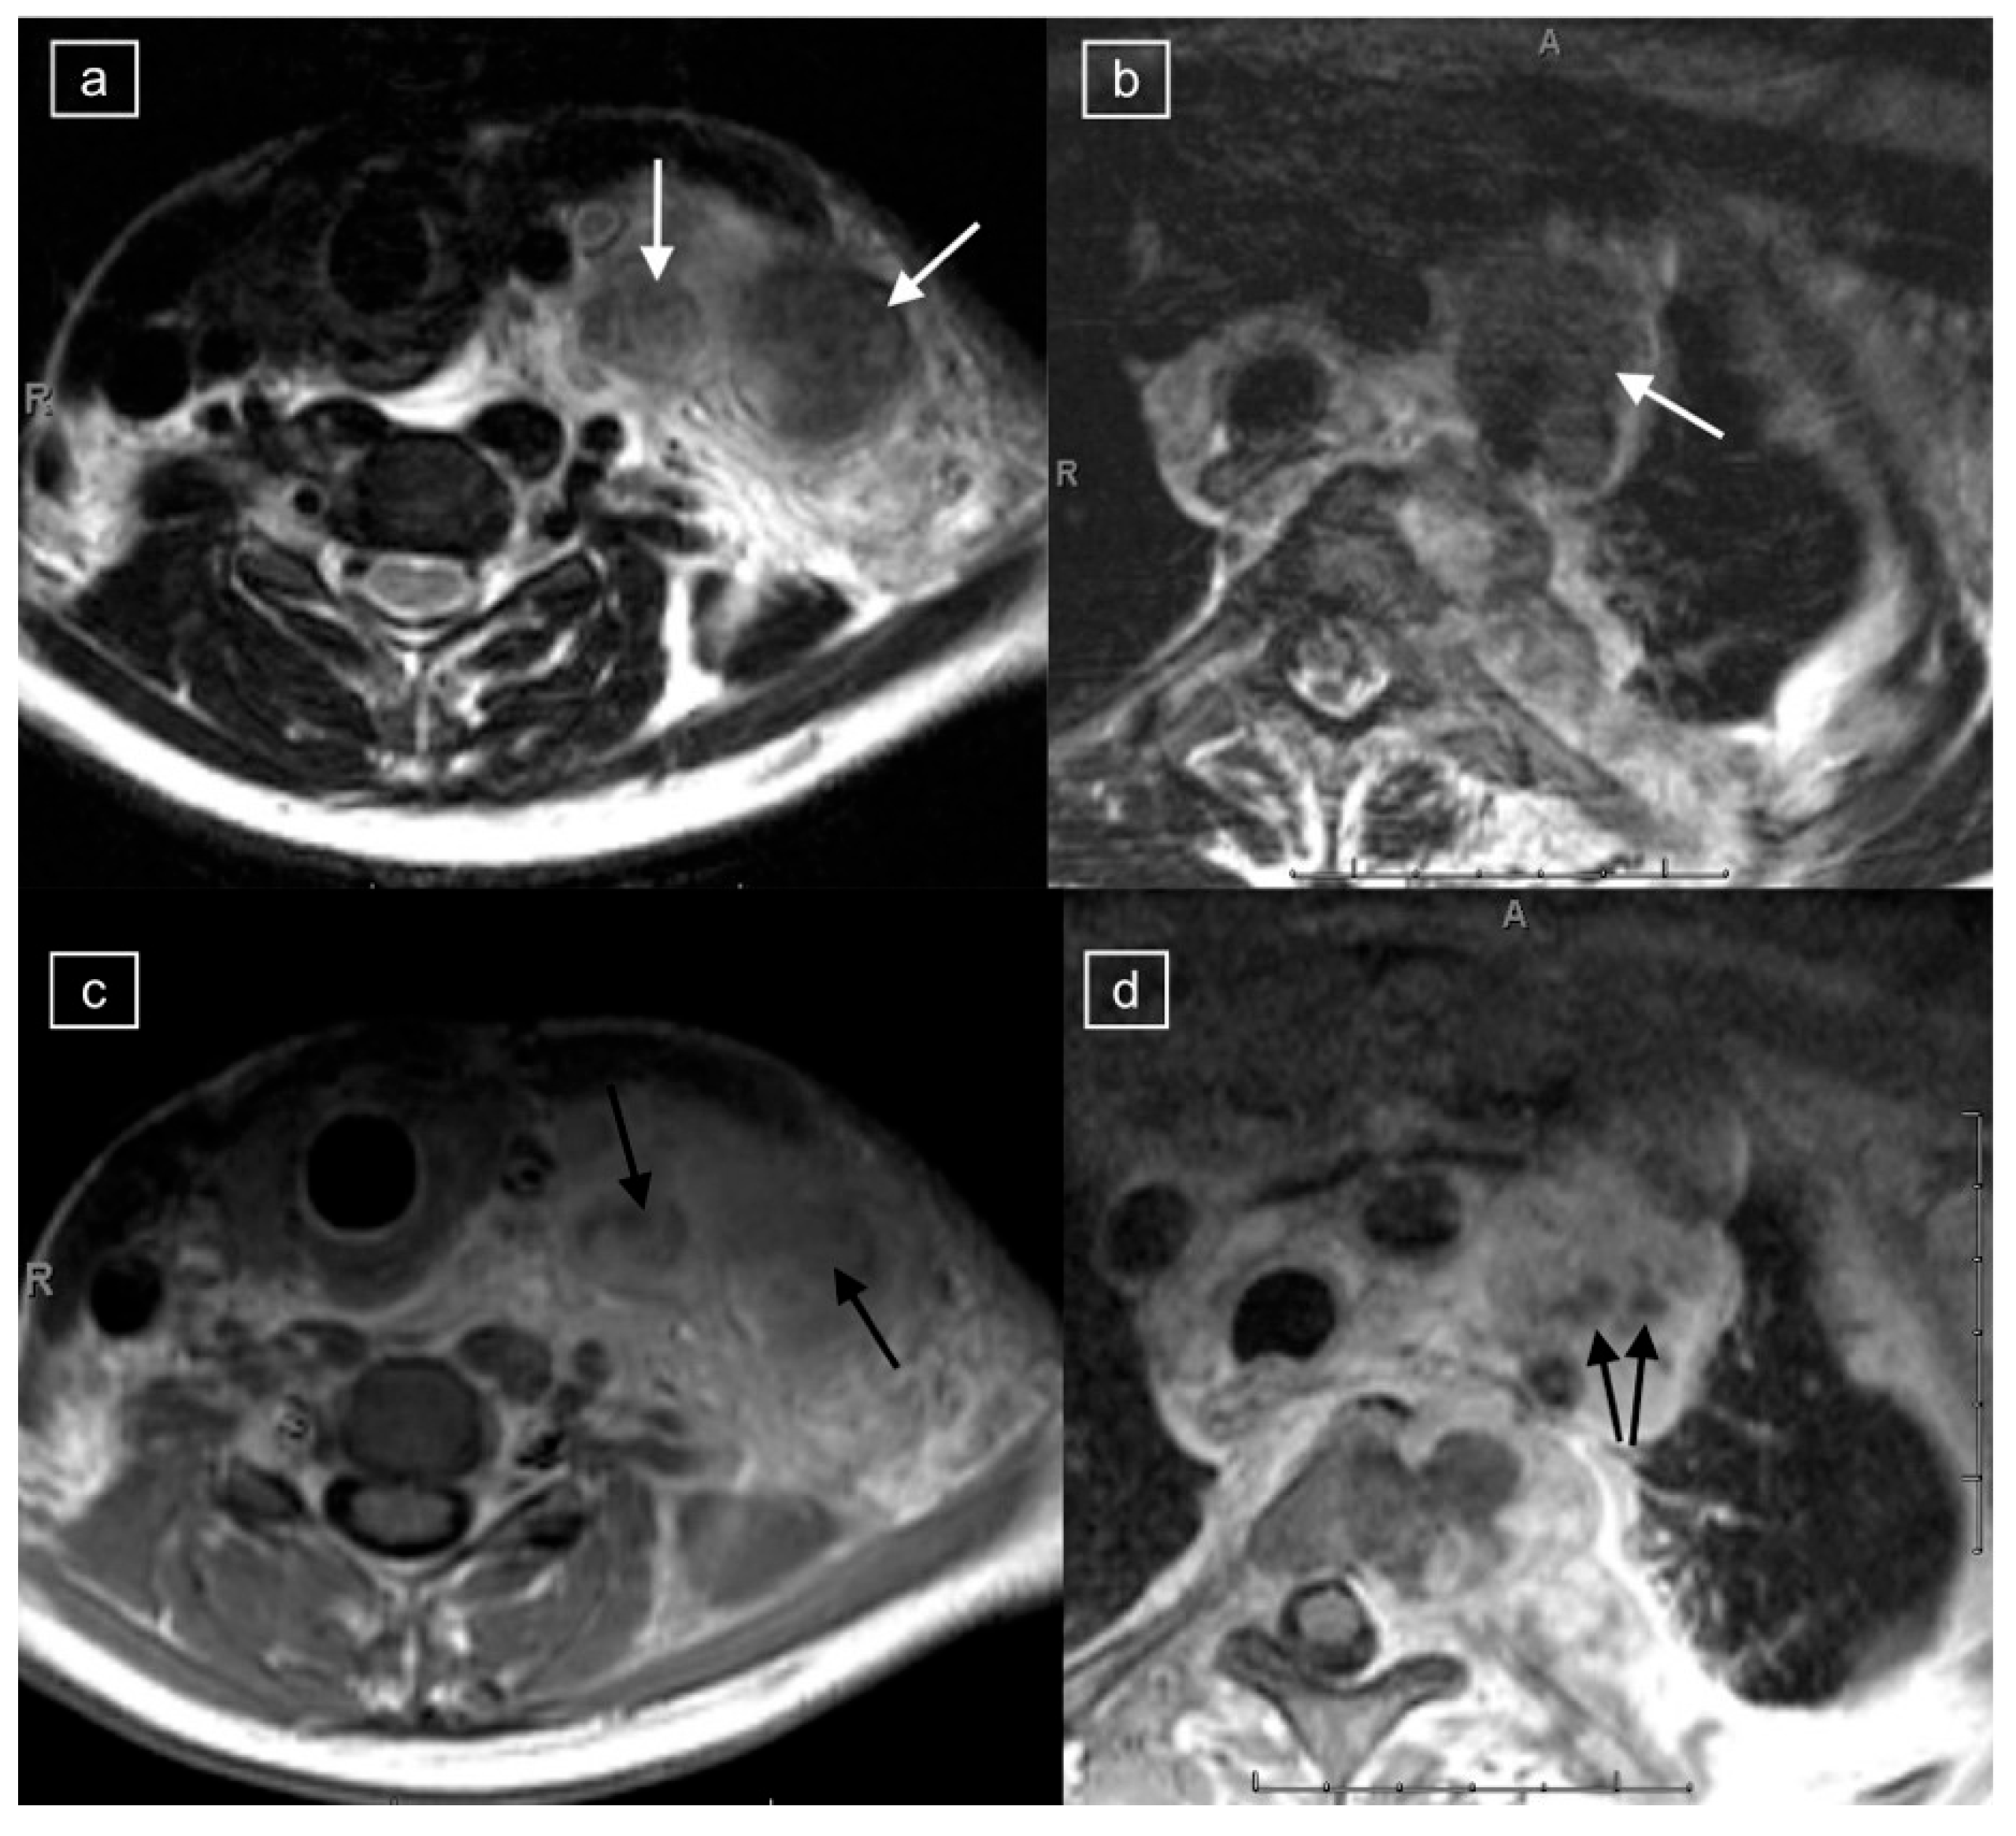

Figure 1.

Magnetic resonance imaging (MRI) in a 20-year-old female with a histologic diagnosis of nodular sclerosing Hodgkin lymphoma. Axial T2-weighted (T2w) images of the lower cervical region (a) and upper mediastinum (b) demonstrate large left cervical and left paratracheal lymphadenopathy (white arrows) exhibiting low T2 signal. On corresponding post-gadolinium T1 imaging of the lower cervical region (c) and upper mediastinum (d), the abnormal lymph nodes show central foci of hypo-enhancement (black arrows).